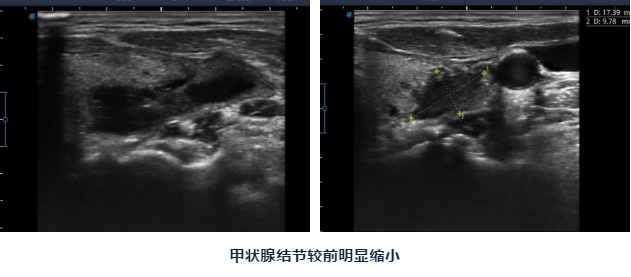

手术在局麻下进行,历时一个多小时就结束了,术后王女士马上就可以下地活动,一个小时后就可以进食,手术的小针眼第二天就基本痊愈,王女士的脖子也看不出肿大了,感觉美观多了。

陈主任告诉王女士,甲状腺结节消融后第二天就可以出院了,之后结节会逐渐吸收、缩小,一般一个月后体积能缩小50%左右,一年后体积能缩小90%以上,小一点的结节可以完全消失,以后按时到医院复查即可。